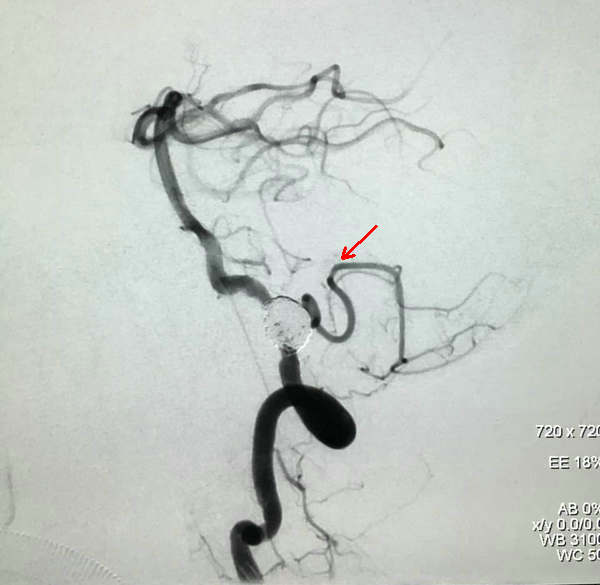

栓塞完成后造影,PICA保留完好(红箭头所示)